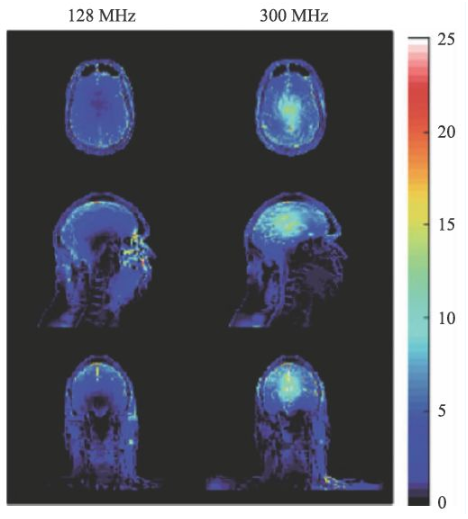

SAR值升高是射頻場(chǎng)另一個(gè)問題,隨著射頻頻率的提高,組織對(duì)射頻能量的吸收急劇上升,可導(dǎo)致組織局部的溫度升高。SAR值的計(jì)算可由式9表示。

σ為組織電導(dǎo)率,ρ為組織密度。對(duì)于SAR值各國(guó)和國(guó)際組織均有嚴(yán)格的限制,因?yàn)檫^量的射頻能量的吸收可能會(huì)對(duì)受試者造成危害。

圖14 是一個(gè)SAR值對(duì)大腦溫度升高的一個(gè)仿真結(jié)果[14],對(duì)于平均SAR=3 W/kg的頭部掃描,7 T(右側(cè))下的溫度升高顯著高于3 T(左側(cè))。因此在超高M(jìn)RI中均需要配置一個(gè)可靠的SAR值監(jiān)控裝置。

圖14 局部SAR值的仿真結(jié)果